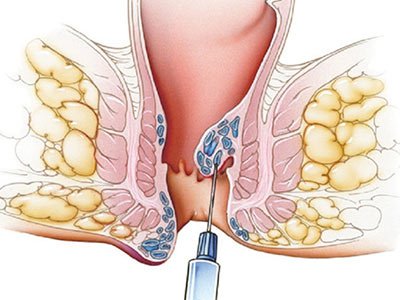

Hemorroidas

Hemorroidectomia tradicional

Ligadura elástica de hemorroidas

Hemorroida a Laser